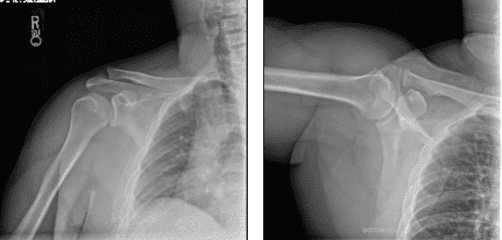

Patient presents shoulder & biceps pain from playing handball. He saw an increasing bulge of right biceps. He also presented his X-ray results, clearly showing the mild to moderate degenerative changes to the right acromioclavicular joint. By this time, we agreed to proceed with treatment options including Physical Therapy, Injection and MRI to identify the real condition of his shoulder.